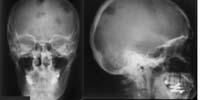

Skelettröntgen (RadioSurf) Interaktive Lernmodule zur Diagnostischen Radiologie des Skeletts für Studierende der Medizin public (öffentlich) Deutsch Studierende 1. Jahr | Studierende 2. Jahr | Studierende 3. Jahr | Studierende 4. Jahr | Studierende 5. Jahr | Studierende 6. Jahr | Ärztinnen/Ärzte in Weiterbildung Tutorial | Quiz | Mustererkennungstraining Website Anatomie

Schädel-CT (RadioSurf) Lernprogramm zu Schädel-CT in Kooperation mit Universitätsklinikum Freiburg i. Br. erstellt. public (öffentlich) Deutsch Studierende 3. Jahr | Studierende 4. Jahr | Studierende 5. Jahr | Studierende 6. Jahr | Ärztinnen/Ärzte in Weiterbildung Mustererkennungstraining Website Radiologie